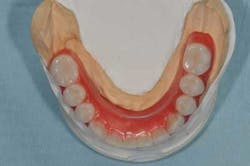

Figs. 9a, b, c: A wax-up is made in the laboratory …

Figs. 10a, b: … and clinically tested for esthetic and functional evaluation. In this case, the wax-up has been quickly turned into a provisional maxillary complete denture.